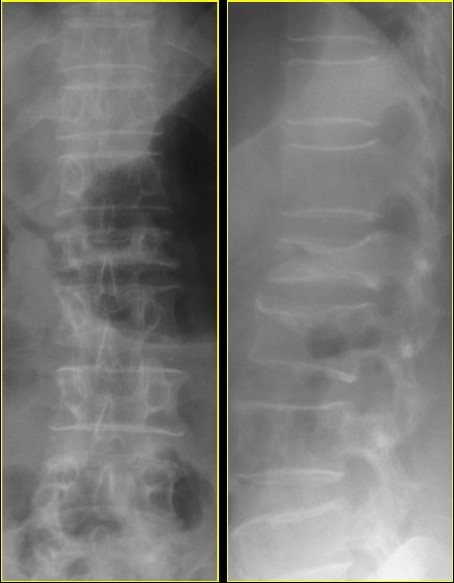

ภาพแสดงกระดูกสันหลังยุบจากโรคกระดูกพรุน

ภาพแสดงกระดูกสันหลังหักจากโรคกระดูกพรุน